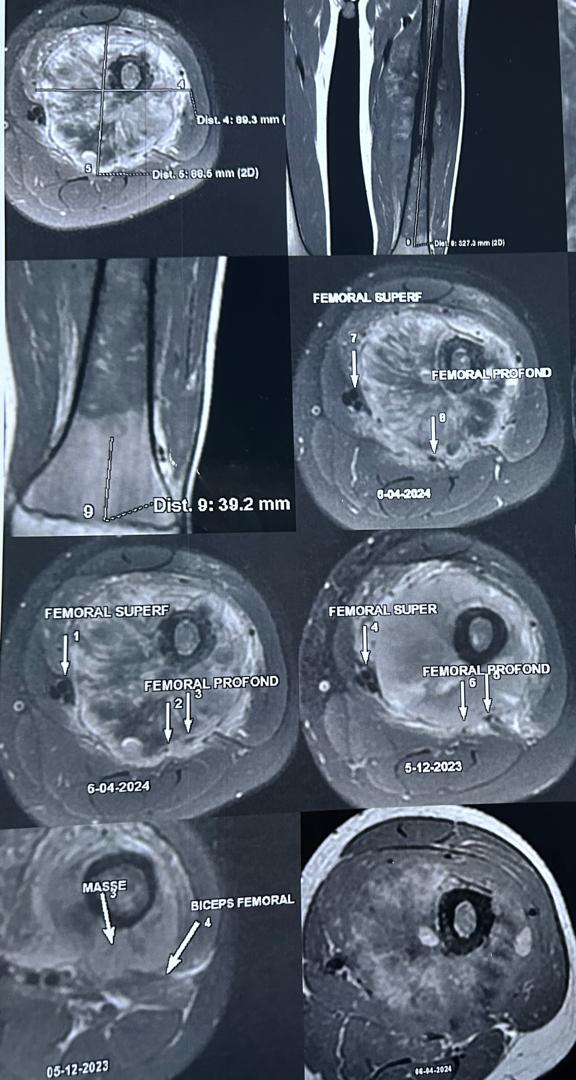

Les signes et symptômes du cancer des os commencent souvent dans un os. Ce cancer affecte principalement les os longs des jambes, et parfois ceux des bras. Les symptômes les plus fréquents comprennent :

- Douleur dans les os ou les articulations. La douleur peut apparaître et disparaître au début. Elle peut être confondue avec des douleurs de croissance.

- Gonflement autour d'un os.

- Chirurgie conservatrice : Retirer la tumeur sans amputer le membre.

- Chimiothérapie : Utilisée après la chirurgie pour traiter les cancers graves.